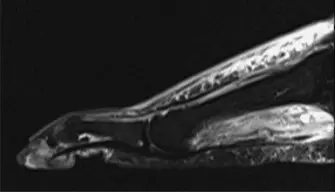

تشخيص تقلص عضلة الساق الخلفية

يعتمد تشخيص تقلص عضلة الساق الخلفية وقرح القدم على تقييم شامل يشمل التاريخ المرضي والفحص السريري الدقيق، بالإضافة إلى بعض الفحوصات التصويرية عند الحاجة. في عيادة الأستاذ الدكتور محمد هطيف في صنعاء، يتم اتباع نهج متكامل لضمان تشخيص دقيق يمهد الطريق لخطة علاجية فعالة.

الفحص البدني الدقيق:

- تقييم الأوعية الدموية: جس النبض في القدم (الشريان الظهري للقدم، الشريان الظنبوبي الخلفي)، زمن إعادة امتلاء الشعيرات الدموية، درجة حرارة الجلد، وجود احمرار. قياس مؤشر الضغط الكاحلي العضدي (ABI) ومؤشر ضغط إصبع القدم العضدي (TBI) ضروريان. يوصى بشدة بقياس ضغط الأكسجين عبر الجلد (TcPO2)، خاصة لدى مرضى السكري، لتقييم حالة الدورة الدموية الدقيقة. إذا اشتبه في وجود قصور وعائي، فإن الإحالة لجراح الأوعية الدموية وإجراء فحوصات تصويرية (مثل تصوير الأوعية) أمر إلزامي.

- التقييم العصبي: اختبار خيوط سيمز-وينشتاين للإحساس الواقي، الإحساس بالاهتزاز (باستخدام شوكة رنانة 128 هرتز)، وخز الدبوس، اللمس الخفيف، الإحساس بالموضع. تقييم الوظيفة الحركية (عضلات القدم الداخلية، العضلات الباسطة والمثنية للكاحل).

الفحص العضلي الهيكلي:

- **اختبار سيلفرسكيولد (Silf